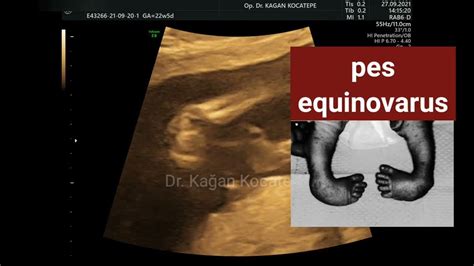

Diagnóza sa zvyčajne stanovuje už pri narodení na základe klinického vyšetrenia. V niektorých prípadoch môže byť deformita identifikovaná aj prenatálne ultrazvukovým vyšetrením. Pri diagnostike sa hodnotí rozsah deformity, pohyblivosť kĺbov a prítomnosť ďalších ortopedických alebo neurologických abnormalít.

Po prvýkrát sa môže ochorenie diagnostikovať počas ultrazvuku, kde si lekár všimne zlú polohu nožičiek. I vďaka tomu je potom možná včasnejšia príprava na prvé kroky v liečbe, ktoré sú mimoriadne dôležité. Vzhľadom na klinické prejavy sa dá pes equinovarus potvrdiť počas tehotenstva na ultrazvuku, nedá sa však popísať charakter vady a stupeň poškodenia chodidla.